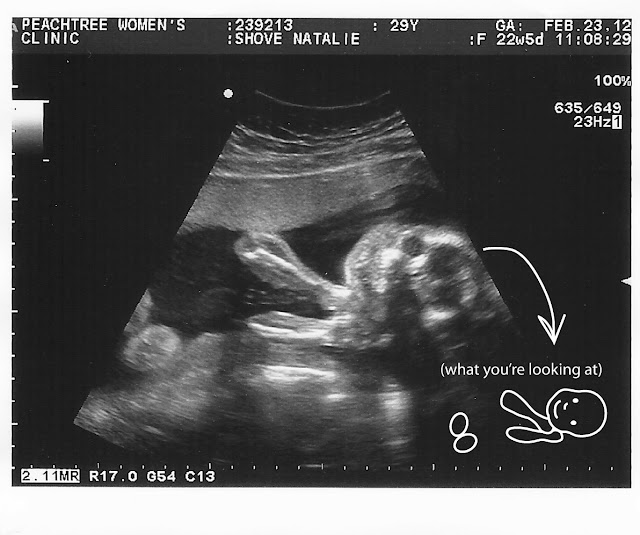

| The baby was SMILING all throughout the “emergency” ultrasound–which calmed my nerves! |

So I went in (twice, actually, because they didn’t have an ultrasound tech in the first day, so they just checked me out and listened to the heartbeat and asked me to come back the next day too) and got a bonus ultrasound! It’s funny how MUCH babies can change even from week to week; this time I could really see the baby’s face in detail on the monitor, almost as clearly as a 3D ultrasound.

Everything turned out to be fine, thankfully. And, for my own peace of mind, I did get an explanation–apparently my bellyflop MANUALLY TURNED the baby 180 degrees, so that it’s no longer breech. Hmmm. No wonder my stomach muscles were a bit perturbed at me! And I couldn’t/can’t feel as much kicking anymore because the baby’s feet are on the opposite side of my body now. So, although I don’t recommend it, I now have a new skill in mothering, just in case the baby flips back to breech between now and June. :)